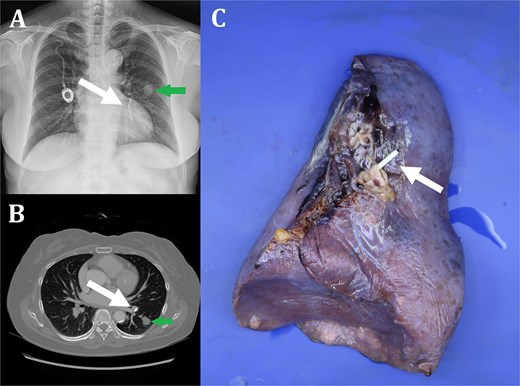

A 59-year-old female presented to our clinic for evaluation of left lung nodule. She underwent surgery for gastric cancer (Stage IIIA) and chemoport was inserted in the right subclavian vein for adjuvant chemotherapy 10 years ago. A chest computed tomography (CT) scan revealed a 1.8 × 1.5 × 1.5 cm lobulating mass with slightly irregular margins in the superior segment of left lower lobe (LLL) (Fig. 1A and B). A CT-guided percutaneous needle biopsy was performed and colloid adenocarcinoma was diagnosed. At the same time, fractured chemoport fragment, which was embedded in left superior segmental pulmonary artery, was also confirmed (Fig. 1A and B). Fortunately, the catheter fragment did not cause any symptoms such as dyspnea or arrhythmia. An F-18-fluoro-positron emission tomography (FDG-PET) showed no evidence of lymph node involvement or distant metastasis. Surgical resection was planned and LLL resection with mediastinal lymph node dissection was performed through uniportal video assisted thoracic surgery. Histopathological findings were consistent with the diagnosis of colloid adenocarcinoma without visceral pleural invasion, lymphovascular invasion, or regional lymph node metastasis, T1bN0M0 (Fig. 2). The chemoport fragment was also removed clearly (Fig. 1C). After lobectomy was completed, the port chamber with proximal catheter segment was removed. The patient had an uneventful postoperative course and was discharged on postoperative Day 5. He has been free of recurrence for 1-year follow-up.

Fractured chemoport fragment embedded in left superior segmental pulmonary artery (white arrow) (A: Chest X-ray, B: Chest CT, C: Specimen of left lower lobe). Colloid adenocarcinoma in superior segment of left lower lobe (green arrow) (A: Chest X-ray, B: Chest CT).